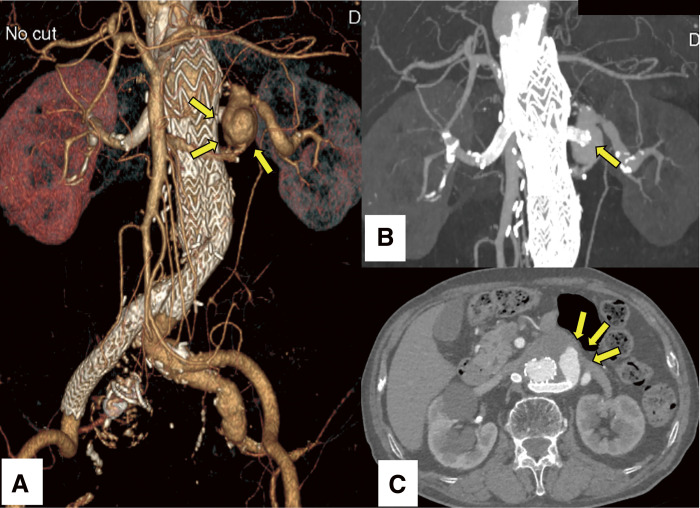

A 78-year-old male presented with progressive enlargement of a pararenal abdominal aortic aneurysm following chimney endovascular aneurysm repair. The aneurysmal expansion was attributed to an endoleak secondary to migration of the left renal artery chimney stent graft, resulting in a 5-mm increase in aneurysm diameter over 6 months. Endovascular reintervention successfully induced aneurysm regression, with no recurrence of endoleak on annual imaging follow-up. While chimney endovascular aneurysm repair presents a minimally invasive alternative for managing complex aortic pathologies, including pararenal abdominal aortic aneurysms, vigilance regarding potential stent graft migration is essential.